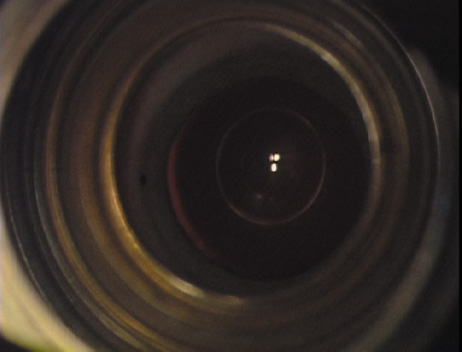

Case 3 is a 48-year-old bilateral hyperope who presented for a refractive surgical consultation. The refraction in his left eye was found to be +3.25 +1.75 × 85. Keratometry was somewhat flat but confirmed WTR cylinder as did corneal topography. Based upon the patient's age, refraction, and somewhat shallow anterior chambers, the decision was made to proceed with a refractive lens exchange. The NAPA nomogram called for LRIs of 55 to 60 degrees with intraoperative pachymetry. Intraoperative keratoscopy confirmed the steep 85-degree meridian (Figs. 2029).

Fig. 20. Keratoscopy, after lifting of the speculum to relieve induced pressure and distortion of the corneal mires, confirms the steep axis of 85 degrees.

Fig. 29. The single-plane RLE incision is completed.